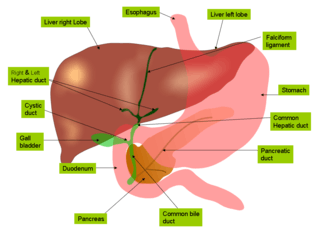

Liver

The liver is the second largest organ (after the skin) and is an accessory digestive gland which plays a role in the body's metabolism. The liver has many functions some of which are important to digestion. The liver can detoxify various metabolites; synthesise proteins and produce biochemicals needed for digestion. It regulates the storage of glycogen which it can form from glucose (glycogenesis). The liver can also synthesise glucose from certain amino acids. Its digestive functions are largely involved with the breaking down of carbohydrates. It also maintains protein metabolism in its synthesis and degradation. In lipid metabolism it synthesises cholesterol. Fats are also produced in the process of lipogenesis. The liver synthesises the bulk of lipoproteins. The liver is located in the upper right quadrant of the abdomen and below the diaphragm to which it is attached at one part, This is to the right of the stomach and it overlies the gall bladder. The liver produces bile, an important alkaline compound which aids digestion.

Bile produced by the liver is made up of water (97%), bile salts, mucus and pigments, 1% fats and inorganic salts.[24] Bilirubin is its major pigment. Bile acts partly as a surfactant which lowers the surface tension between either two liquids or a solid and a liquid and helps to emulsify the fats in the chyme. Food fat is dispersed by the action of bile into smaller units called micelles. The breaking down into micelles creates a much larger surface area for the pancreatic enzyme, lipase to work on. Lipase digests the triglycerides which are broken down into two fatty acids and a monoglyceride. These are then absorbed by villi on the intestinal wall. If fats are not absorbed in this way in the small intestine problems can arise later in the large intestine which is not equipped to absorb fats. Bile also helps in the absorption of vitamin K from the diet. Bile is collected and delivered through the common hepatic duct. This duct joins with the cystic duct to connect in a common bile duct with the gallbladder. Bile is stored in the gallbladder for release when food is discharged into the duodenum and also after a few hours.[25]

Gallbladder

The gallbladder is a hollow part of the biliary system that sits just beneath the liver, with the gallbladder body resting in a small depression.[26] It is a small organ where the bile produced by the liver is stored, before being released into the small intestine. Bile flows from the liver through the bile ducts and into the gall bladder for storage. The bile is released in response to cholecystokinin (CKK) a peptide hormone released from the duodenum. The production of CKK (by endocrine cells of the duodenum) is stimulated by the presence of fat in the duodenum.[27]

It is divided into three sections, a fundus, body and neck. The neck tapers and connects to the biliary tree via the cystic duct, which then joins the common hepatic duct to form the common bile duct. At this junction is a mucosal fold called Hartmann's pouch, where gallstones commonly get stuck. The muscular layer of the body is of smooth muscle tissue that helps the gallbladder contract, so that it can discharge its bile into the bile duct. The gallbladder needs to store bile in a natural, semi-liquid form at all times. Hydrogen ions secreted from the inner lining of the gallbladder keep the bile acidic enough to prevent hardening. To dilute the bile, water and electrolytes from the digestion system are added. Also, salts attach themselves to cholesterol molecules in the bile to keep them from crystallising. If there is too much cholesterol or bilirubin in the bile, or if the gallbladder doesn't empty properly the systems can fail. This is how gallstones form when a small piece of calcium gets coated with either cholesterol or bilirubin and the bile crystallises and forms a gallstone. The main purpose of the gallbladder is to store and release bile, or gall. Bile is released into the small intestine in order to help in the digestion of fats by breaking down larger molecules into smaller ones. After the fat is absorbed, the bile is also absorbed and transported back to the liver for reuse.

Pancreas

The pancreas is a major organ functioning as an accessory digestive gland in the digestive system. It is both an endocrine gland and an exocrine gland.[28] The endocrine part secretes insulin when the blood sugar becomes high; insulin moves glucose from the blood into the muscles and other tissues for use as energy. The endocrine part releases glucagon when the blood sugar is low; glucagon allows stored sugar to be broken down into glucose by the liver in order to re–balance the sugar levels. The pancreas produces and releases important digestive enzymes in the pancreatic juice that it delivers to the duodenum. The pancreas lies below and at the back of the stomach. It connects to the duodenum via the pancreatic duct which it joins near to the bile duct's connection where both the bile and pancreatic juice can act on the chyme that is released from the stomach into the duodenum. Aqueous pancreatic secretions from pancreatic duct cells contain bicarbonate ions which are alkaline and help with the bile to neutralise the acidic chyme that is churned out by the stomach.